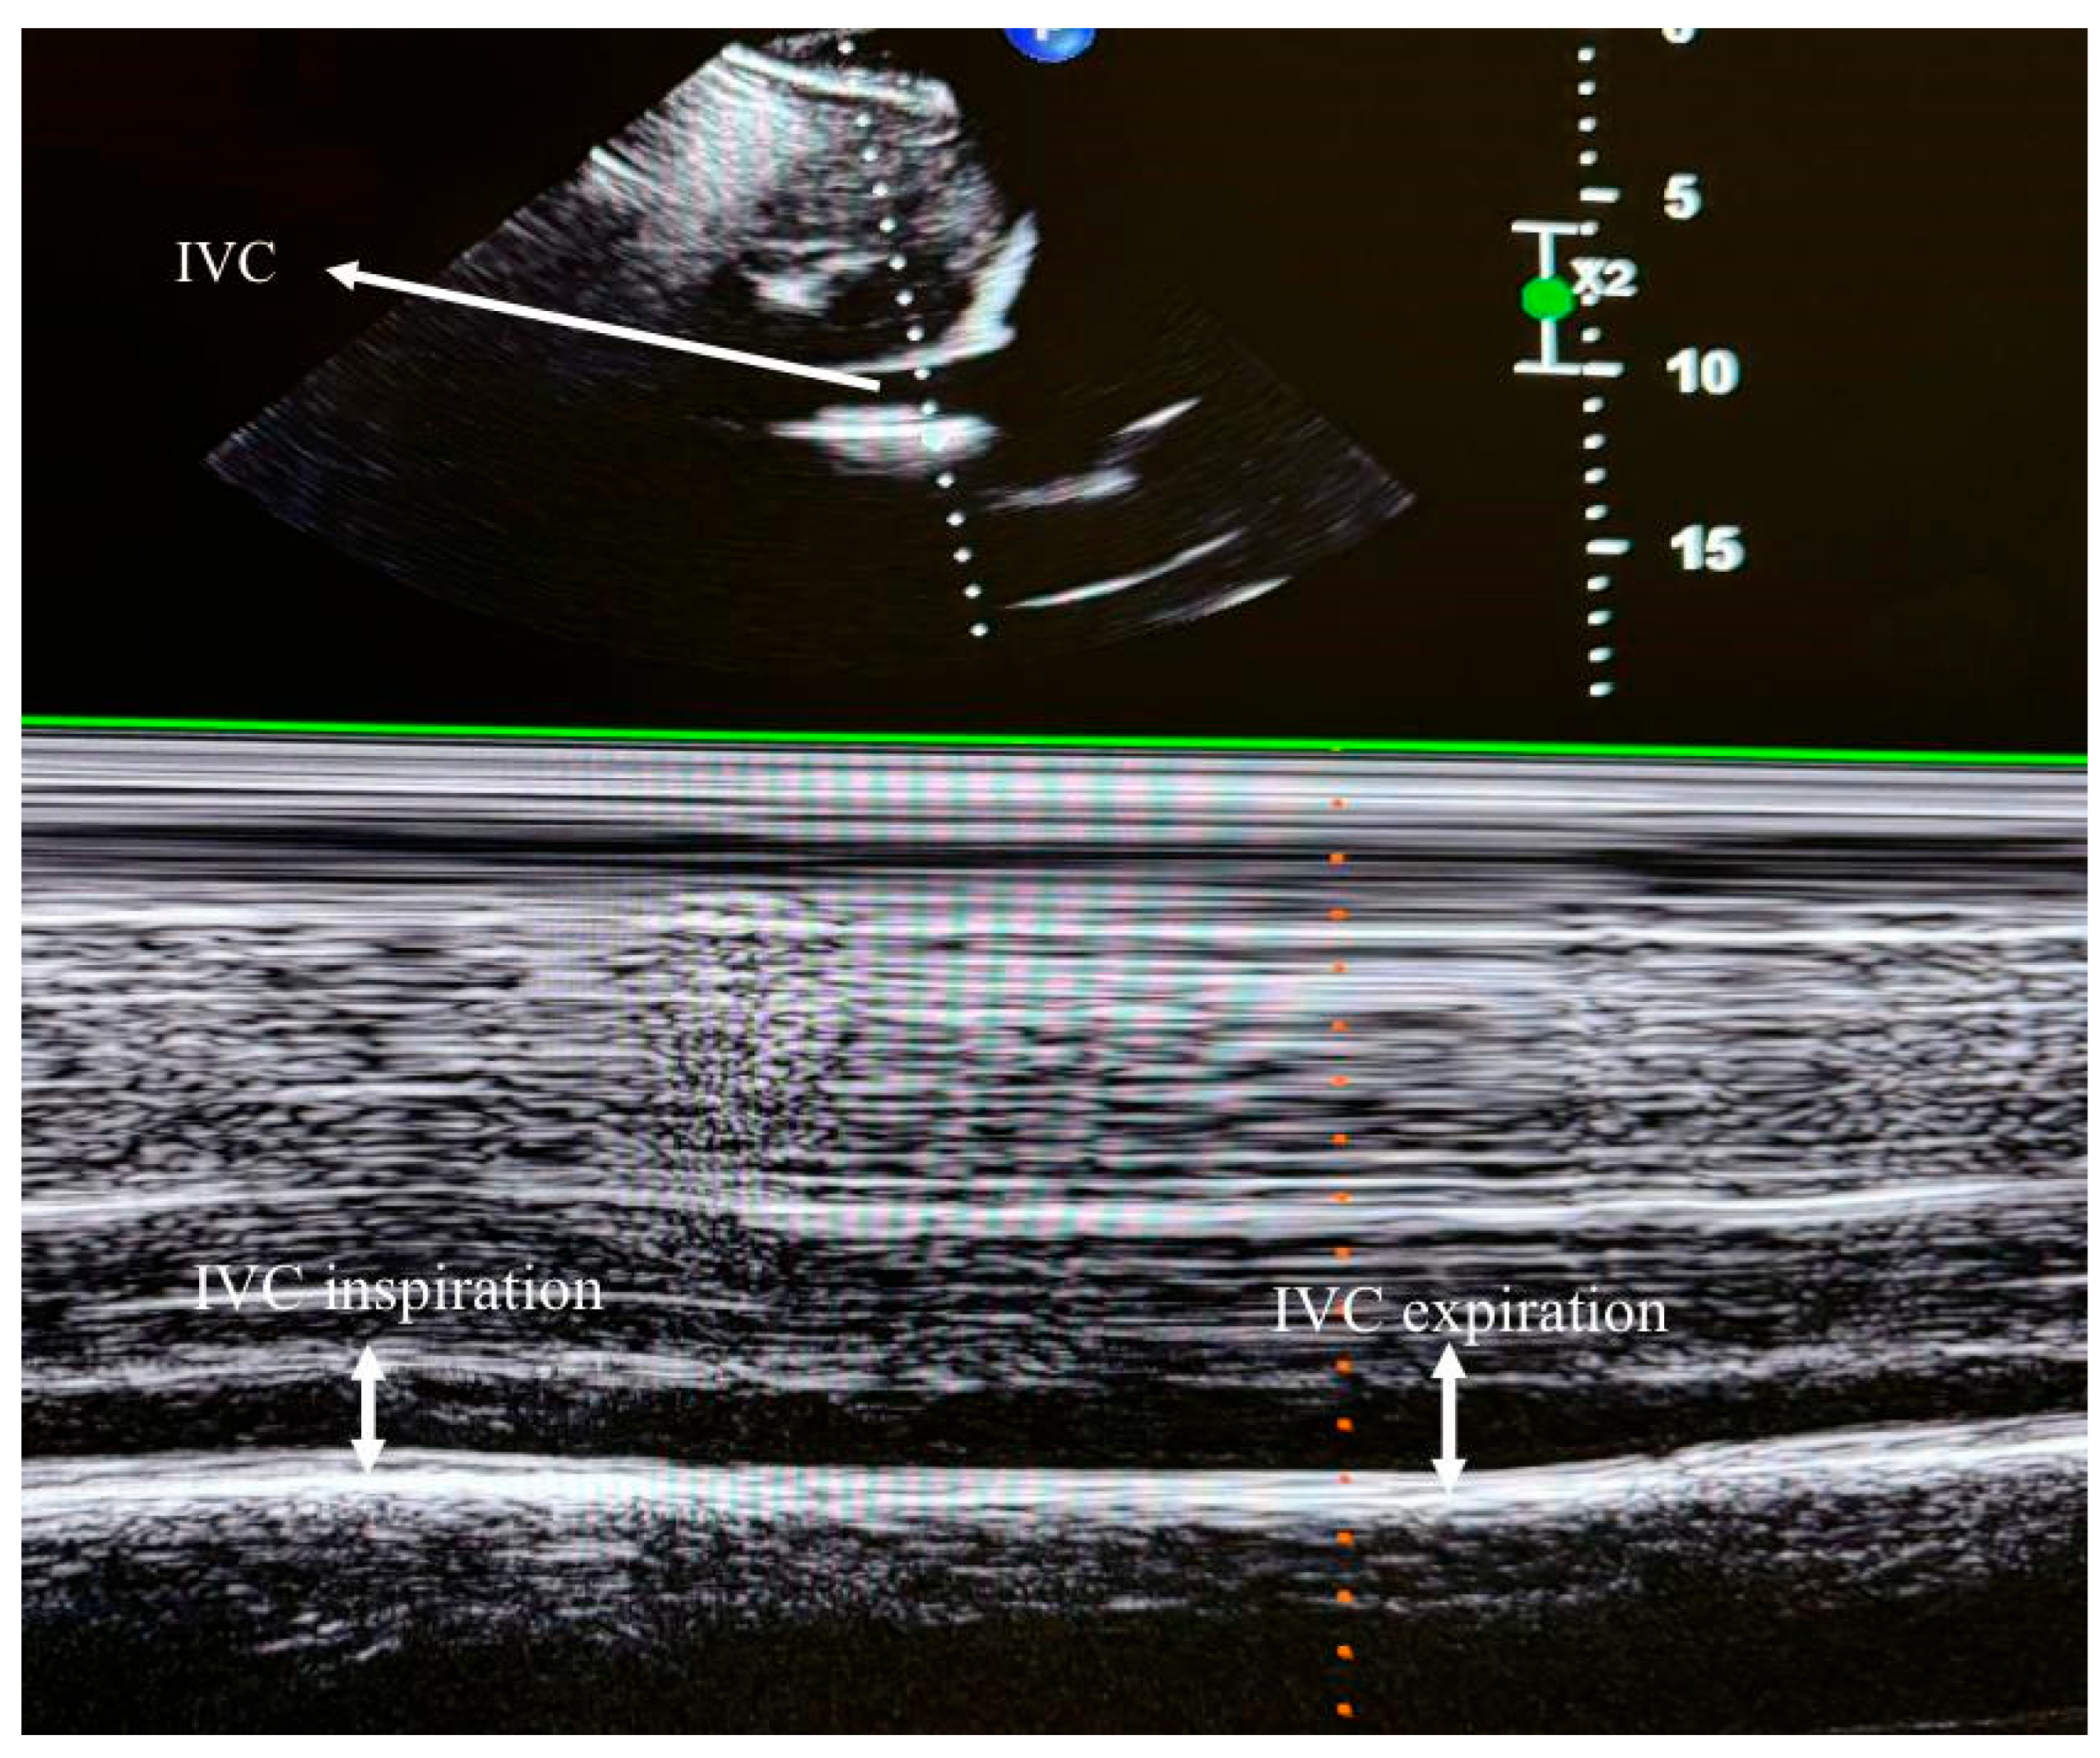

To assess RV systolic function, myocardial performance index (MPI), fractional area change (FAC), TAPSE, and TDI-derived indices were measured. RV diastolic function was evaluated using tricuspid E and A wave velocities and the E/A ratio. TAPSE was obtained by placing an M-mode marker along the tricuspid annulus and measuring its longitudinal motion at peak systole. Ejection time (ET), isovolumetric relaxation time (IVRT), and isovolumetric contraction time (IVCT) were derived from TDI images. The MPI was calculated as a global index of RV function using the formula MPI = (IVCT + IVRT)/ET. Tricuspid regurgitation (TR) was assessed using color Doppler interrogation in the apical four-chamber view. A well-defined continuous-wave (CW) Doppler TR signal was obtained for the accurate determination of the peak tricuspid regurgitant velocity (TRV) (Figure 2). IVC measurements were performed in the supine position using a subxiphoid approach. The cursor was placed 1 cm distal to the hepatic vein–IVC junction, and the IVC diameter was monitored for 30 s in M-mode. Measurements were recorded at peak inspiration (IVCins) and peak expiration (IVCexp) during normal breathing (Figure 3). The IVC collapsibility index (IVC-CI) was calculated using the formula: IVC-CI = (IVCexp − IVCins)/IVCexp.

Figure 2. Transthoracic echocardiographic image showing tricuspid peak velocity.

Figure 3. Transthoracic echocardiographic image depicting inferior vena cava (IVC) diameters.